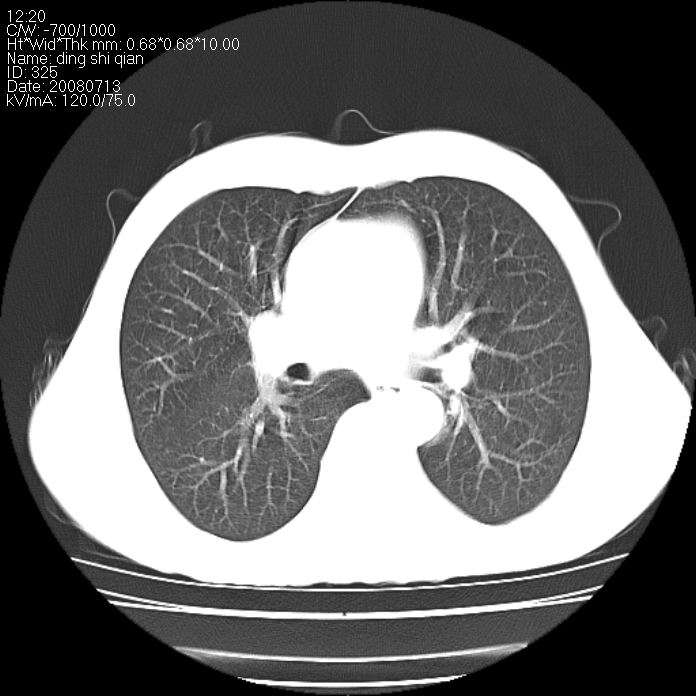

标题: CT14654:男 50岁 近来胸痛 [打印本页]

标题: CT14654:男 50岁 近来胸痛

右侧上肺块状软组织影,浅分叶,边缘毛刺证,与胸膜粘连,考虑:周围性肺癌

右侧上肺块状软组织影,浅分叶,边缘毛刺证,与胸膜粘连,考虑:周围性肺癌!支持!

典型右肺周围型肺癌